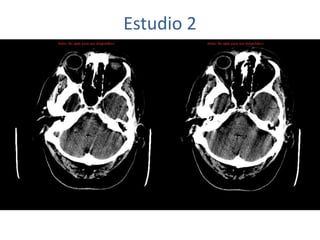

Estudio 2

• Estudio sin y con contraste, con reconstrucciones sagitales y coronales

del estudio con contraste.

Se observa una lesión ocupante de espacio en lóbulo frontal derecho que

presenta un tamaño de 18 x 32 x 22 mm (cc x ap x tr), bilobulada, no del

todo bien delimitada, con realce en anillo irregular, con hipocaptación

central, probablemente por necrosis, y asociada a un extenso edema

vasogénico con efecto masa tanto sobre los surcos de la convexidad

como sobre la cisterna insular, el sistema ventricular y la línea media,

esta última con un desplazamiento de 5 mm a la altura del septo

interventricular.

No se aprecian otras lesiones focales intra o extraaxiales de significación

patológica.

Habría que considerar como primera posibilidad que se tratase de una

lesión metastásica, por bien un tumor primario, aunque no se puede

descartar otras opciones, sin imprescindible correlación con la clínica y

con sus antecedentes.